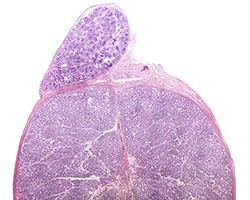

Órganos Linfoides

Órganos Linfoides

Ganglio linfático, bazo y timo.

(8 preparaciones) -